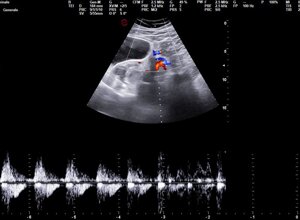

ECOGRAFIA ADDOME